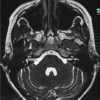

U dây VIII

» Thông tin: Nữ giới – 35 tuổi.

» Lâm sàng: Điếc đột ngột.